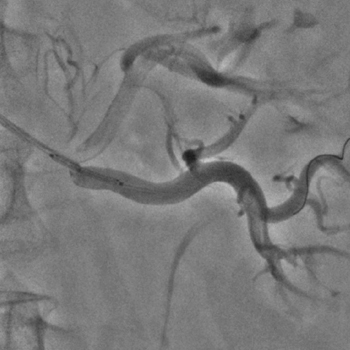

Бифуркационное стентирование почечной артерии

Ангиографическое исследование аорты и селективная ангиография сосудов почек выявило критический стеноз a. segmenti inferioris и короткую a. renalis sinistra